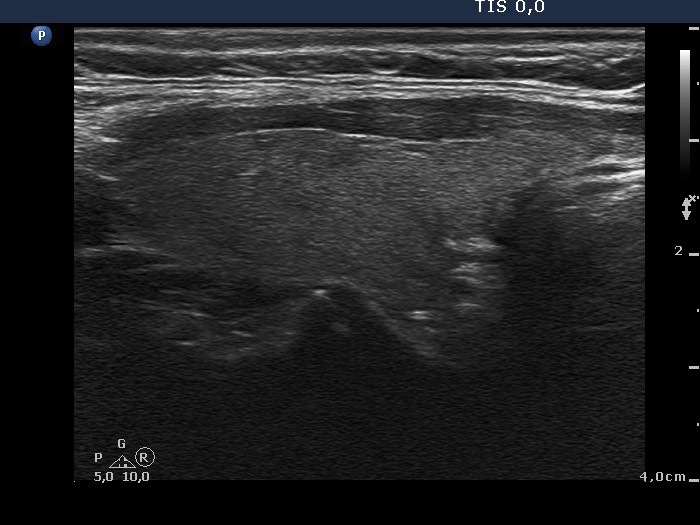

100 consecutive cases of papillary cancer - case 031 (ultrasonographic picture 2)

Right lobe, longitudinal scan.